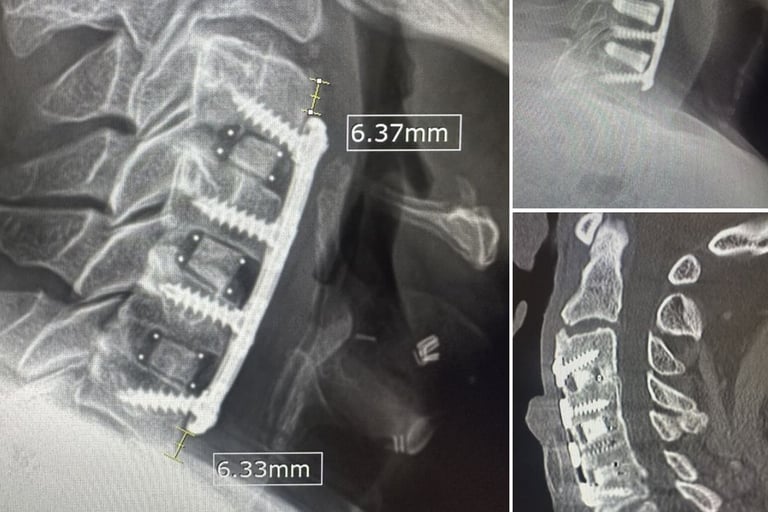

Case #3: ACDF Print

This is a PETG translucent print for a past ACDF surgery, and I wanted to print out real-life, slightly larger parameters to explore the importance of them in surgeries. In this LinkedIn post, surgeons commented on slightly larger parameters for plates being of interest in ACDF cases. In this back-tested case, I found that a slight increase in depth and size leads to slightly stronger plates (due to bending moment) by validating my print via compression and ultimately better use of screws with inserters (insertion).

As this example and previous ones demonstrate, in each of my prints, I have been using parameters (either public or user-defined) to mimic real-life conditions. The next step for me is to incorporate metallic injections (utilizing injection molding). These prints provide a good foundation for this approach, and the mold angle and cavity sizes are the next steps in my career when it comes to product development in this space. Below are the anatomical regions I have also printed to give me reference to validate anatomical fit when working on cases in my free time.